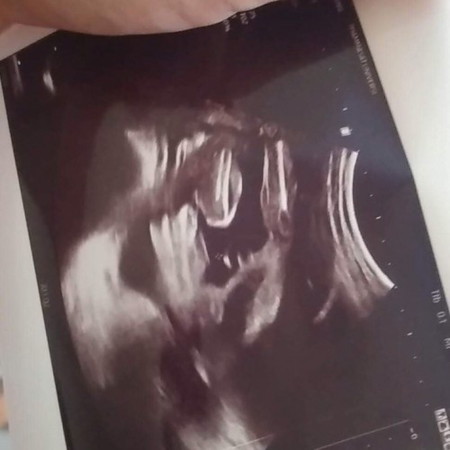

ผู้หญิงหรือผู้ชายค่ะ

แม่ๆช่วยดูให้หน่อยค่ะน้องเป็นผู้ชายหรือผู้หญิงค่ะ แต่คุณหมอบอกน่าจะผู้หญิง ไม่แน่ชัดค่ะ